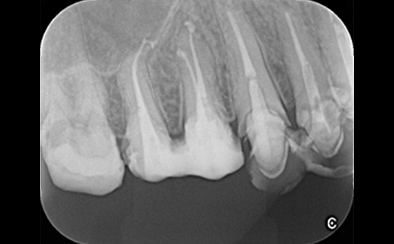

治療前

治療後

黄色い矢印の歯が治療前の対象歯です。レントゲンで観察すると、歯の根のお薬が充分には入っていないようです。

麻酔をして歯の中をマイクロスコープで観察すると、元々あった3つの根だけでなく「もう一つの4番目の根」があったのです。根管治療自体は容易に行えましたが、歯の中を明るく拡大できるマイクロスコープを持っていない歯医者さんでは見つけるのが困難だと思われます。この4つ目の歯の根を治療することにより痛みは消失し「抜歯してインプラント」になるという悪循環に陥らず済みました。根管治療はマイクロスコープを使って精密に、また丁寧に行えば歯を長く保たせることができる治療です。やはり神経自体を残すという選択が、歯の保存にとって一番良いということは間違いありません。

| 費用 | デンタルドック:55,000円 根管治療(奥歯):176,000円 MTAセメント:33,000円 歯の土台:33,000円 合計:297,000円 |

| リスク・副作用 | 治療中に一時的な咬合痛や冷温水痛、若干の歯肉の腫れ、発赤などを生じることがあります。また仮歯の時期には仮歯の脱離や破損の可能性、舌感などに違和感を覚えることがありますが、本歯に移行するまでに通常消失します。 ※すべて症例による違いや個人差があります。 |

※表示金額は全て税込みです。